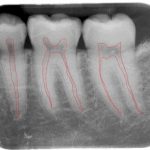

A root canal is commonly your last option to save a tooth. In the very center of the tooth are all of the nerves, blood vessels, and other tissues called the pulp. This part of the tooth is alive. When there are problems with this part of the tooth, the ability to heal itself is quite poor. For this reason, the dentist “kills” the tooth on purpose to avoid these problems from getting worse. The picture below shows the pulp of a tooth outlined in red.

The tooth is killed by removing the vital part of the tooth found in small thin canals using files. The canals are then widened by using progressively larger files. It is important for the files to clean within 1 mm of the tip of the root but not beyond. The canals are then sterilized with a substance called sodium hypochlorite. Finally, the canals are then plugged with a rubber material called gutta percha. A successfully completed root canal allows people to keep their teeth for decades longer. The following picture shows a completed root canal.